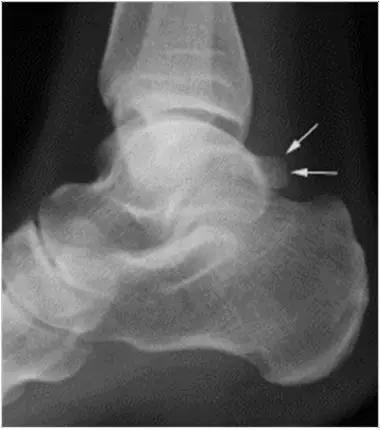

男,11岁,自述后踝下方疼痛,活动时为甚,并有一突起。

- 踝关节正侧位X 线平片,侧位片均显示距骨后方有三角形或椭圆形的距后三角骨。部分病例伴有轻度的踝关节骨性关节病。

- MRI 检查示距后三角骨及周围软组织有水肿信号,距后三角骨和距骨之间正常的低信号纤维连接中断,出现液性信号。

- 三角籽骨或距骨后三角结构模糊和变形,T1WI信号降低, T2WI信号升高,